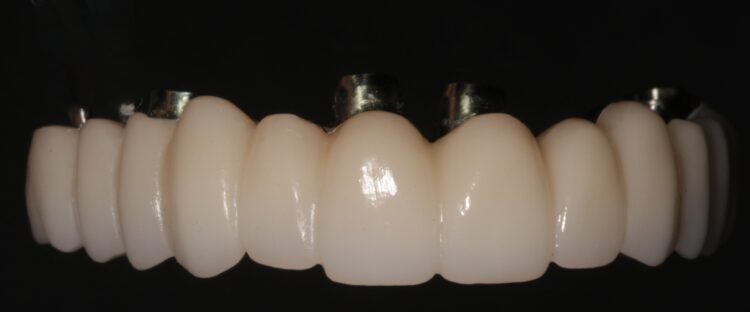

A titanium substructure was digitally designed (Bridge Base by Atlantis) taking into consideration the functional and aesthetic virtual wax-up and emergence profile as the FP1 provisional prosthesis shaped it. This metal substructure was anatomically shaped at the gingival and occlusal sides in order to tightly adhere at the soft tissue interface leaving at least 2mm of clearance for the zirconia superstructure.

Based on the digital design and copying the approved provisional prosthesis, a zirconia overlay was milled. The overlaying zirconia superstructure was digitally designed to fit the metal substructure, accomplish a flawless finish line, avoid any undercuts and verify the path of insertion, thus facilitating the bonding procedures. The zirconia superstructure was bonded with the titanium substructure using a self-curing luting composite. The final polished screw-retained prosthesis was delivered and torqued to 30Ncm and the radiographic assessment was executed.

The translucent zirconia supported by titanium framework fulfils the aesthetic and mechanical requirements of an FP1 full arch prosthesis, while minimising the risk of fracture by providing a rigid yet passive joint to support the implants.[vi] The zirconia and titanium transmucosal surface characteristics (otherwise known as biocompatibility) create a highly polished interface for high cell adhesion and optimised gingival architecture.